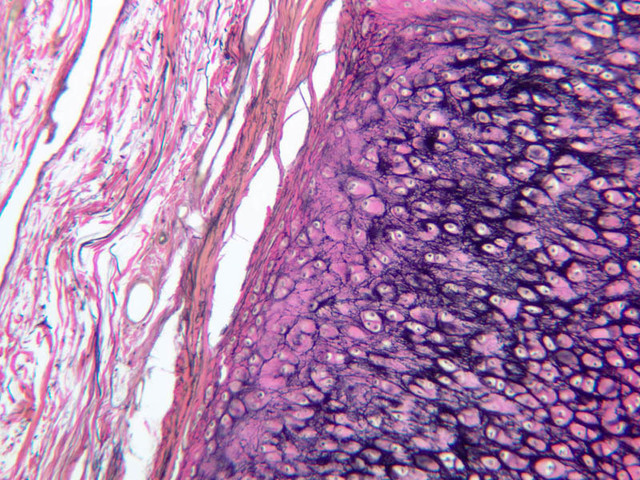

Elastic cartilage (A-51, H&E [2.5x, 10x, 20x, 40x]; A-51, Verhoeff stained for elastic fibers [2.5x, 10x, 20x, 40x] [2.5x, 10x, 20x, 40x]) is similar to hyaline cartilage, but with elastic fibers in the matrix. Verhoeff's stain is specific for elastic fibers. Other features of this tissue resemble hyaline cartilage: perichondrium, lacunae with chondrocytes, and matrix basophilia. Note the absence of blood vessels in the cartilage. In H&E stained tissue, the elastic fibers cannot be visualized. Where can elastic cartilage be found?

Fibrocartilage (A-3, H&E [2.5x-labeled, 10x, 20x, 40x-labeled] [2.5x, 10x, 20x, 40x]). Examine the section of tissue from the intervertebral disc. This tissue is fibrocartilage, the least abundant form of cartilage. Fibrocartilage appears as small nests of chondrocytes embedded in a fibrous connective tissue. It is found where cartilage is subject to pressure, (i.e., intervertebral discs). This type of cartilage occurs as a transition between tendon and bone and perhaps for this reason it does not have a perichondrium. Only the rounded lacunae show clearly that this tissue is cartilage. As with the other types of cartilage, chondrocytes produce and maintain the extracellular matrix. Matrix with a higher concentration of proteoglycans, indicated with darker staining, can be seen immediately around the lacunae—territorial matrix. Areas with a lower concentration of proteoglycans stain less intensely—interterritorial matrix.